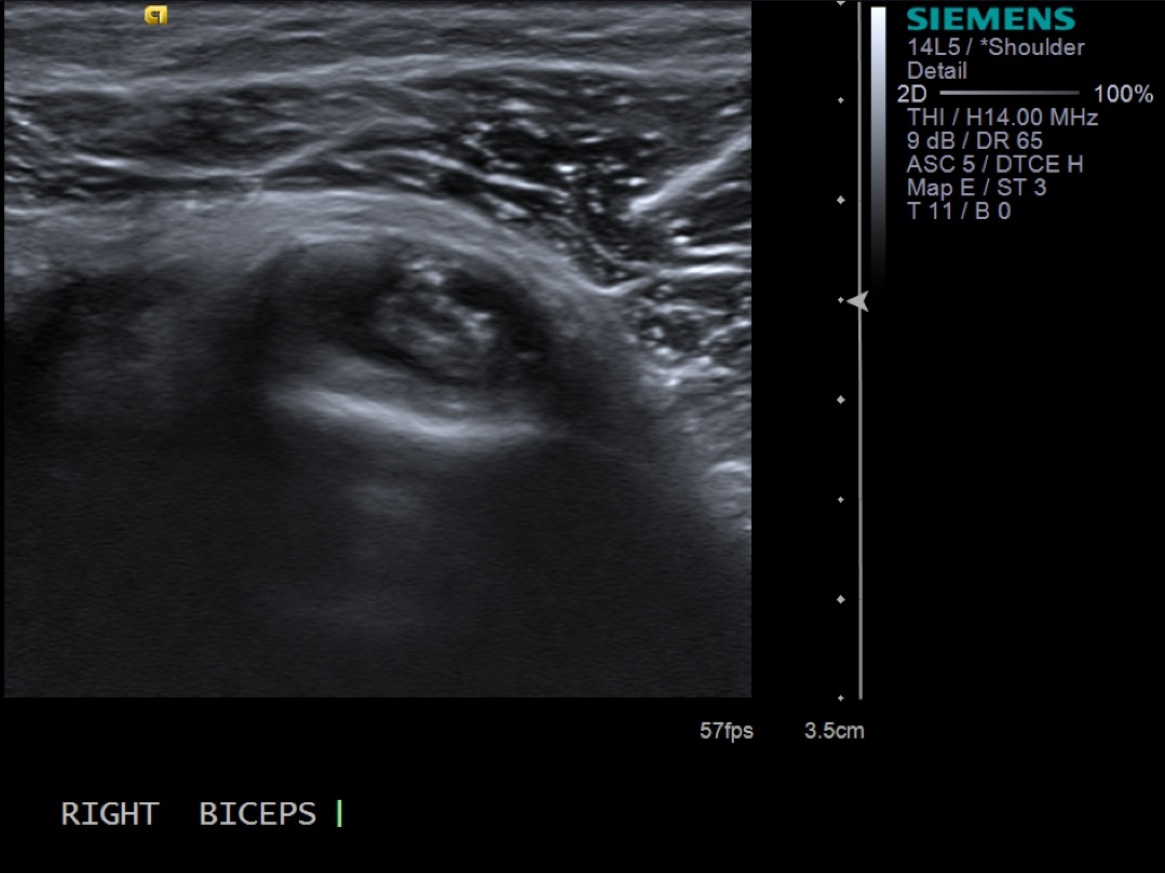

3. Scan patient looking at the biceps tendon (short axis/transverse) extra-articular and at the rotator interval. If there is fluid in the biceps tendon sheath when extra-articular, you can inject at that site. Otherwise, will need to inject at the rotator interval.

• descriptiondescription

Extra-articular biceps tendon in transverse plane

Biceps Tendon in the Rotator Interval